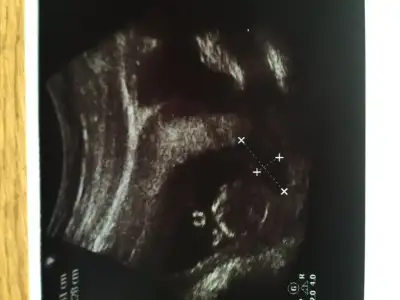

Baska resim var mı canım sırtı dönük tam çıkıntıya işaret koymuş

Kız sen nerden anlıyon sırtı dönük. Ben hiçbişi görmüyomBaska resim var mı canım sırtı dönük tam çıkıntıya işaret koymuş